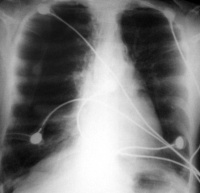

一、X线检查:胸廓扩张,肋间隙增宽肋骨平行,活动减弱,膈降低且变平,两肺野的透亮度增加。

诊断根据病史、体检、X射线检查和肺功能测定可以诊断科研。X射线检查表现为胸腔前后径增大,胸骨前突,胸骨后间隙增宽,横膈低平,肺纹理减少,肺野透光度增加,悬垂型心脏,肺动脉及主要分支增宽,外周血管细小。肺功能测定表现为残气、肺总量增加、残气/肺总量比值增高、1秒率显著降低、弥散功能减低。